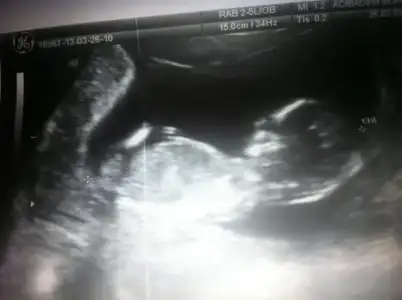

dr soylemeden siz gorun genital nub teorisi ( bebegin cinsiyeti)

canim dr un kiz demis ama ilki kiz gibi ikinci resimm ise bariz erkekk

doğru bu haftalar yanıltabiliyor dr.ları.dr.uma çok güveniyorum bulunduğum ildeki sayılı iyi kadın doğumculardan ama neticede o da insan.yanılabilir... ben bu ihtimalden korkuyorum açıkçası..dr.ekrana iyice baktı evirdi çevirdi bize bacak arasını gösterdi.sanki anlıyomuşum gibi:))bacak arası açık büyük ihtimal kız bu dedi.bi arkadaşıma da dr.u bacak arası açıksa kız olur demiş.onunki de kızdı.

bi de pipi göremedim dedi.küçükse onu bilemem 2 hafta sora daha net konuşurum dedi.eşim ısrar etti.tamamdır kız bu dedi.dr öyle emin konuştu ki açıkçası ben de eşim de kız diye düşündük...erkenden sevinmiyim ben yine kız diye..Allah hayırlısını versin..hepimize...